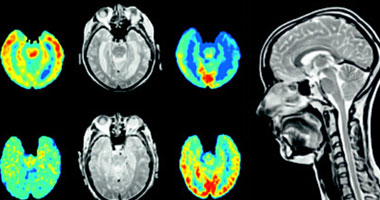

قام الباحثون بفحص دقيق لأدمغة أشخاص أصحاء تتراوح أعمارهم بين 8-86 عاما، المدهش أن المشاركين الذين لديهم شكل معين من هذا الجين لديهم نقص فى مساحة المادة البيضاء فى المخ عن غيرهم، وتعتبر المادة البيضاء هى اتصالات المخ، وهى مهمة للذاكرة ومهارات التفكير العليا، لوحظ هذا الأمر حتى فى أصغر المشاركين.

ثم تفحّص الباحثون فى أنسجة مخ 189 متوفيًا من الذين لم يكن لديهم مرض الزهايمر، وتتراوح أعمارهم بين أقل من سنة إلى 92 سنة، وأولئك الذين لديهم النسخة المعينة من الجين أظهروا خللا فى عملية ترجمته إلى بروتينات.

وأيضا حلل الفريق أنسجة مخ 710 أشخاص، تتراوح أعمارهم بين 66-108 أعوام، وكان معظمهم ممن يعانون من اضطرابات معرفية خفيفة، أو مرض الزهايمر، أظهرت النتائج أن هذا الجين بصورته الخطرة مرتبط مع بروتين (بيتا أميلويد).